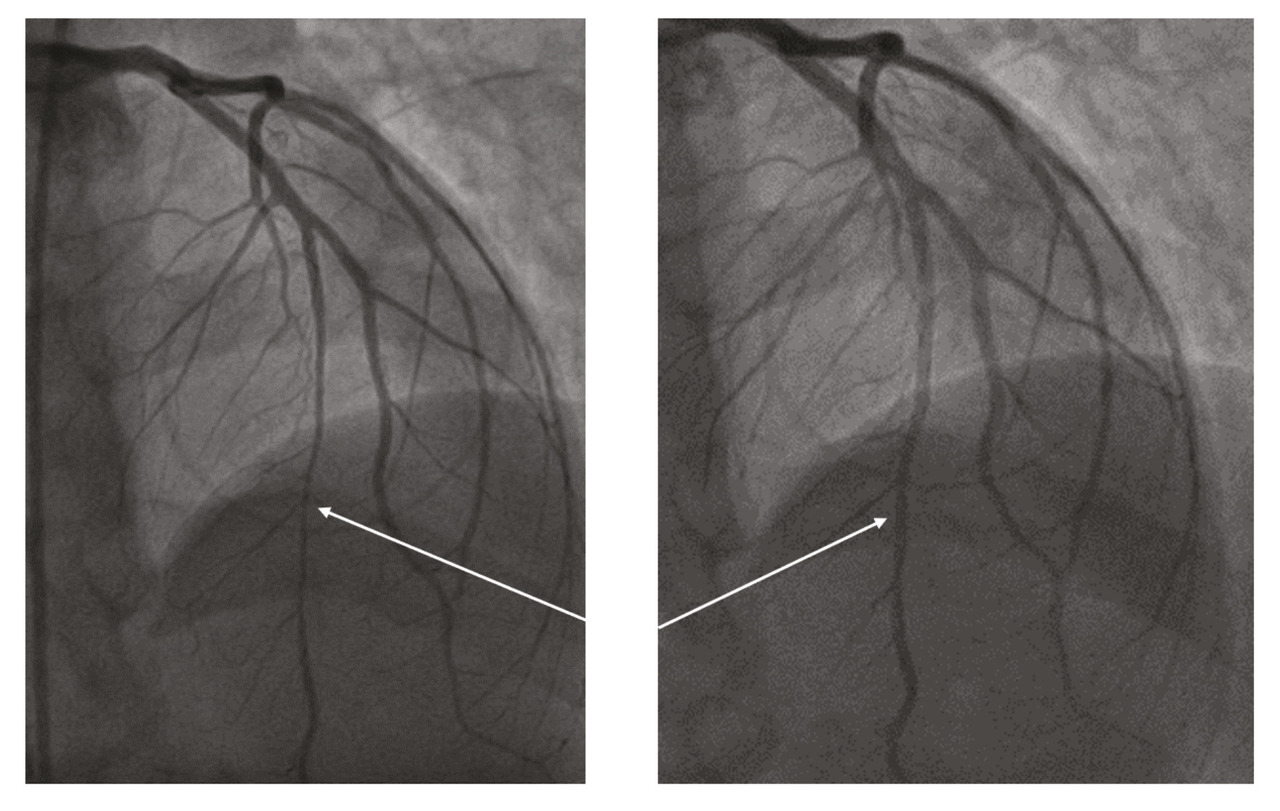

Elle revient de façon programmée deux mois plus tard pour une nouvelle coronarographie avec imagerie intracoronaire et test de provocation pour spasme coronarien. L’imagerie intracoronaire retrouve un athérome au niveau du segment proximal et moyen de l’artère interventriculaire antérieure (IVA). Le test de provocation (injection de méthylergométrine) provoque un spasme coronarien au niveau de I’IVA, résolutif après injection de dérivés nitrés (fig. 4). Le traitement est renforcé par ajout d’un deuxième dérivé nitré.